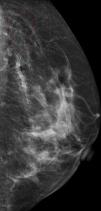

Presentamos el caso de una paciente de 52 años, con antecedentes familiares de carcinoma de mama (madre), que acudió a realizarse una mamografía anual de control en la cual se apreciaron microcalcificaciones de distribución lineal siguiendo los pliegues cutáneos, de predominio en el cuadrante superoexterno mamario y ambas regiones axilares (fig. 1).

Por ello, en estos pacientes no resulta excepcional observar, mediante radiografía simple y mamografía, imágenes de densidad calcio, que pueden distribuirse linealmente, secundarias a la calcificación de las fibras elásticas de la pared de los vasos sanguíneos, y/o como microcalcificaciones mamarias y axilares, debido a la calcificación de las fibras elásticas de la dermis3, e incluso se ha postulado que dichas microcalcificaciones mamarias puedan ser resultado de la calcificación de la fascia muscular y los septos interlobulares glandulares5.

Según el estudio de Bercovitch et al., se detectan microcalcificaciones mamarias en más de la mitad de las mujeres con PXE. En la mayoría de los casos estas calcificaciones parecen distribuirse de forma aislada, aunque en algunos pacientes6 se han descrito formando agrupaciones a modo de conglomerados de contenido cálcico que justificarían la palpación de nódulos en ambas axilas, tal y como ocurrió en nuestro caso. Aunque es muy característico encontrar en estos pacientes la combinación de microcalcificaciones mamarias y calcificaciones vasculares, y no es raro encontrar estos hallazgos radiológicos en la población normal, la presencia de ambos debe hacernos valorar minuciosamente la piel, por si existiesen alteraciones sugestivas de PXE. Se ha observado que las calcificaciones que afectan a las estructuras vasculares que contienen tejido elástico pueden apreciarse hasta en un tercio de los pacientes mediante radiografía simple5 y, al calcificarse las arterias coronarias, la sintomatología simula la originada por la arteriosclerosis.

En definitiva, aunque toda calcificación objetivada en una mamografía puede representar a priori un signo de alarma, es importante conocer la frecuencia de asociación de las microcalcificaciones mamográficas con el PXE y tenerlo en cuenta de cara al diagnóstico diferencial con el carcinoma mamario7,8.